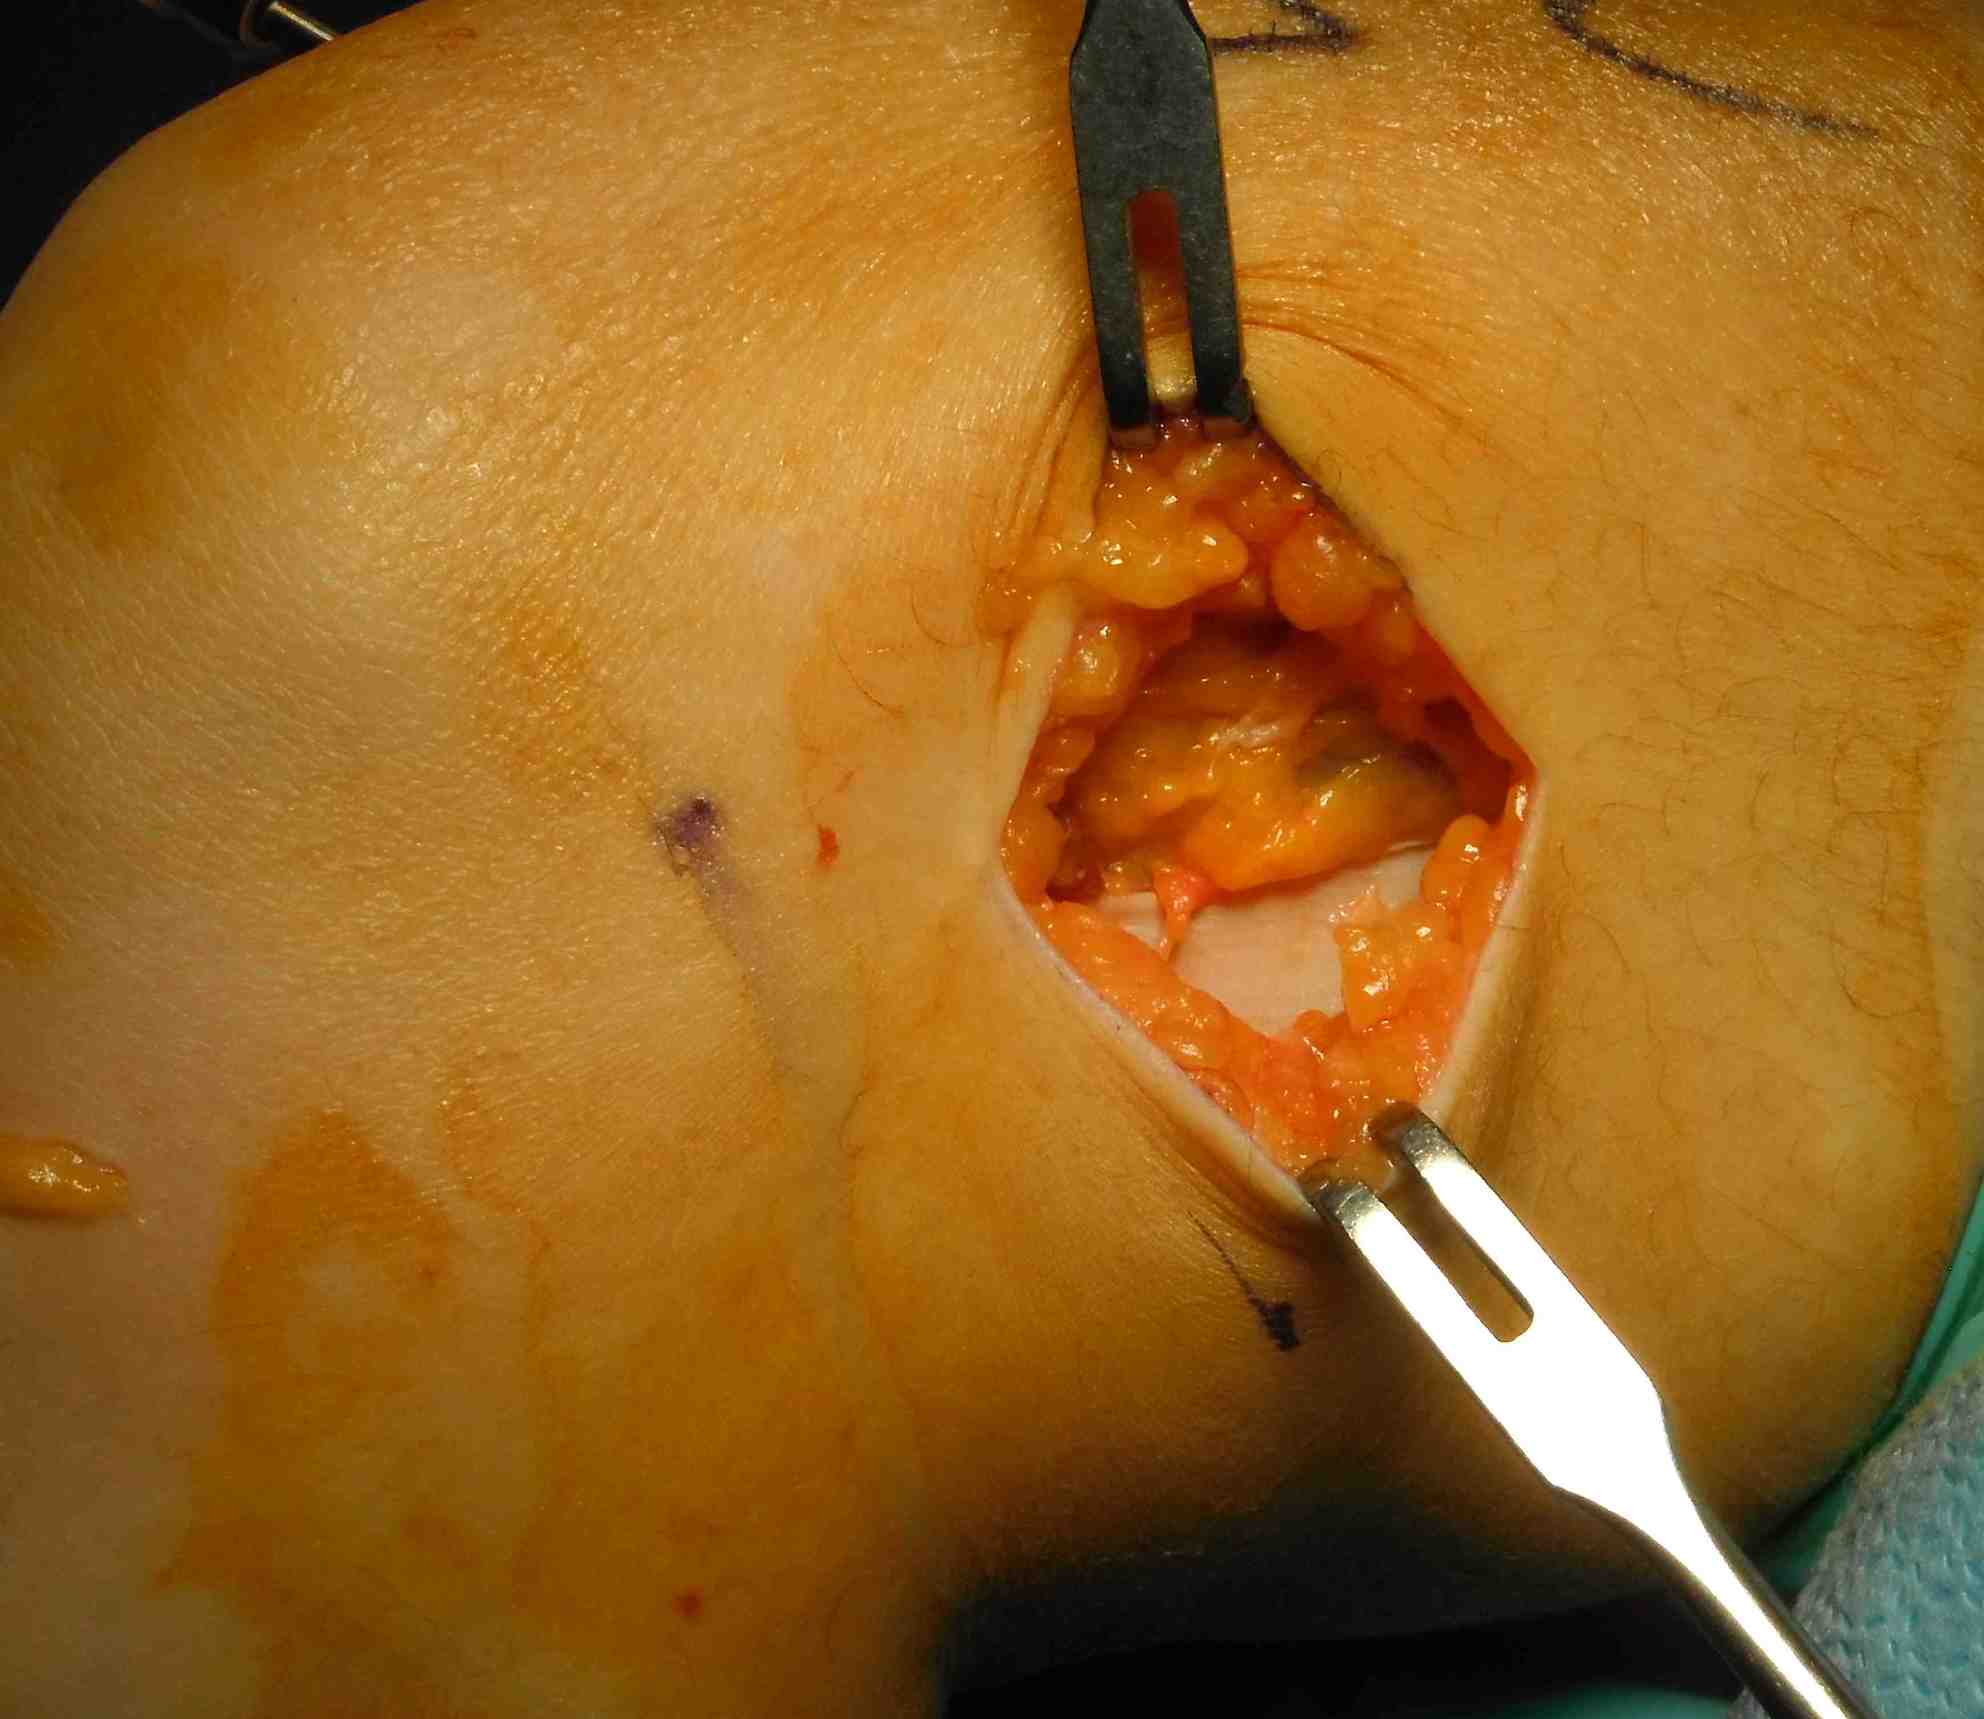

Need to make second incision in ITB

- pass graft anteriorly

- so can staple to femur